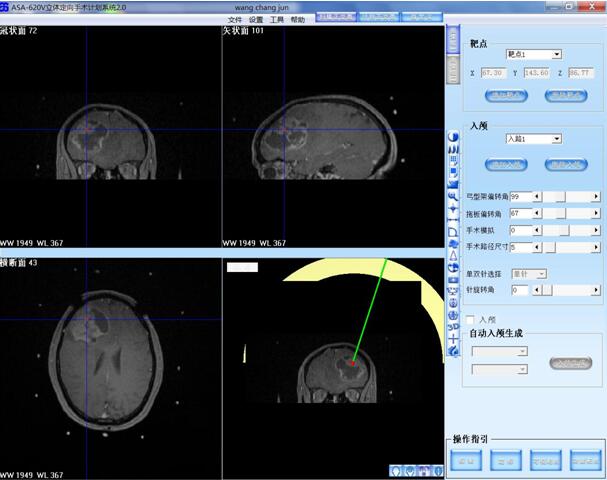

患者王某某,男,53岁,因“间断头痛半月”入神经内科十二病区,发现颅内占位后转入神经外科。既往患者有肺Ca病史,于一年前行手术治疗。头颅影像学诊断胶质瘤?转移瘤待排。2016年6月29日在3.0T磁共振定位后,刘增强副主任与其团队为患者实施了立体定向脑内病变活检术,此患者病灶为囊实性,手术难度较大,而一旦囊液流失则会发生脑组织漂移,导致靶点移位,因此手术计划制定尤为重要,入颅点为右额部,穿刺后首先达到肿瘤实性部分,获取病灶标本后,抽出部分囊液以缓解患者高颅压症状,经过精细的手术操作,最终成功获取肿瘤标本,并且抽出约20ml肿瘤液,患者情况稳定,术后两小时即下床活动。

我院在2015年度科研立项经费总额达59万的基础上,今年又启动了新一轮院内科研基金项目,并对基金项目的分设进行了重新梳理和分层、定位,基金项目分为三大类型:科技助推计划基金、研究生科研创新计划基金、科学研究专项基金。其中科技助推计划资助以临床常见、重大、疑难疾病的预防、诊断和治疗需求为牵引,以最终获得具有临床应用价值的诊疗方法和标准,以及应用新仪器、新器械为目标而开展的应用研究,资助金额为30-50万元/项,研究期限3年;“立体定向颅内病变活检术”属于我院2016年度院内科学研究基金项目中的助推计划,是我院重点扶持和推动的项目,立项经费达30万元。本项目立项后,医院立即按照课题计划,购置了目前国内应用最广的安科立体定向设备及手术操作计划系统,通过电生理记录、获取组织标本、制造毁损灶、消除病变等方法,以达到进行生理研究、诊断和治疗中枢神经系统疾病的目的。目前神经外科应用立体定向技术已开展颅内病变活检,深部血肿穿刺,囊性病变囊液抽吸,脑脓肿穿刺抽吸及腔内治疗。尤其对于颅内囊实性恶性肿瘤可以留置Ommaya囊进行治疗。